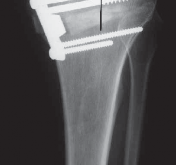

18. Delayed postoperative

1. Patella baja

2. Nonunion or delayed union

3. Hardware failure (

FIG 4C

)

4. Collapse with loss of osteotomy correction (

FIG 4D–F

### FIG 4 • A. Lateral cortical breach stabilized with a three-hole 1/3 tubular plate. This was placed after the osteotomy had propagated through the lateral wall of the tibia. B. Intra-articular extension of the osteotomy that was not repaired intraoperatively, with subsequent osteotomy collapse and hardware breakage. C. Hardware failure. There is no collapse of the osteotomy, but the distal screws failed secondary to micromotion.

### FIG 4 •

(continued)

D–F. Collapse of the osteotomy with loss of correction. D. One-week postoperative image with mechanical axis at lateral tibial spine. E. Four-month postoperative image with significant osteotomy collapse (4 degrees of varus). F. Ten-month postoperative image with final osteotomy collapse into 10 degrees of varus. The patient started off with a 15-degree varus deformity.**